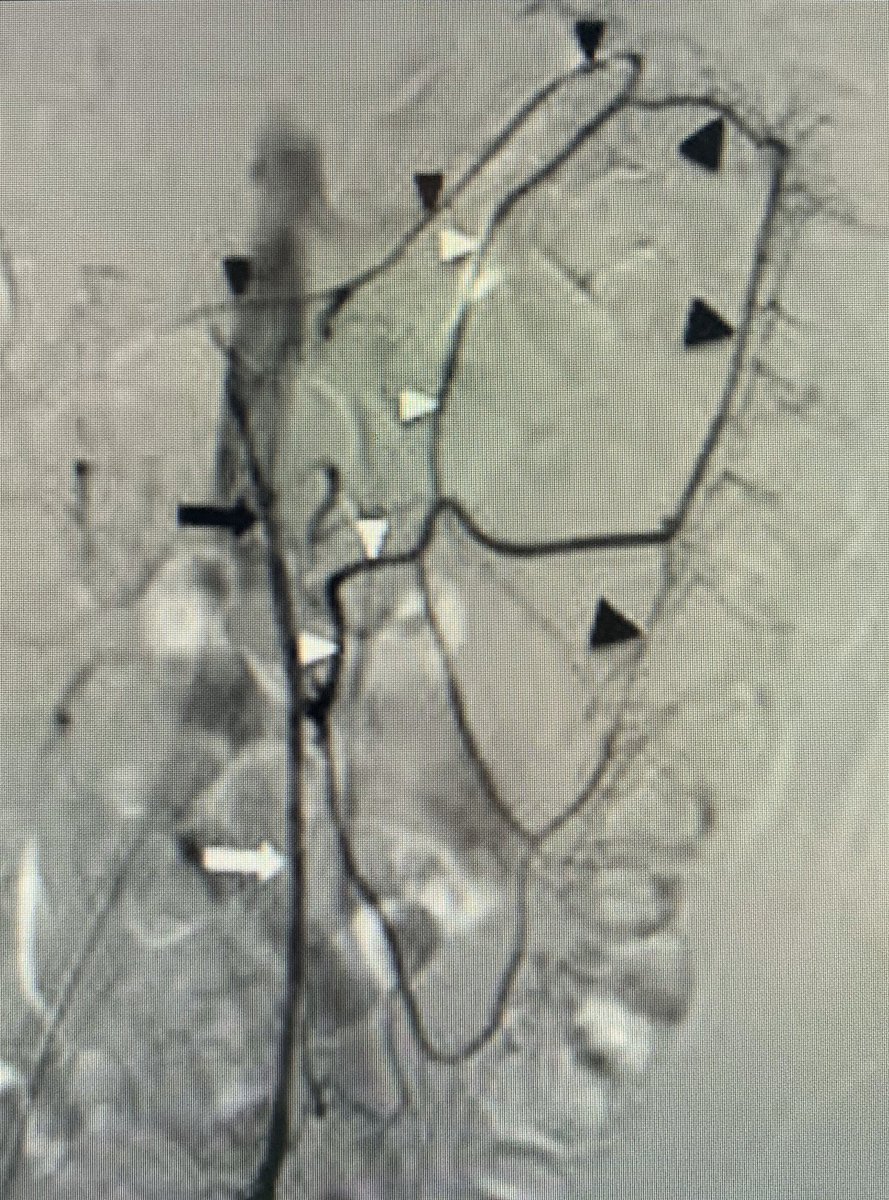

@MountSinaiIR Our R3s are gearing up for the ABR Core Exam, we will post relevant#IRad cases/info weekly starting NOW! 1. Name the arterial collateral pathways btw the Celiac Artery

SMA?

2. What about for the SMA

IMA? #CoreIR#FOAMrad#FOAMed#radres#IRadRes#MedEdpic.twitter.com/YaCv0jOL7r